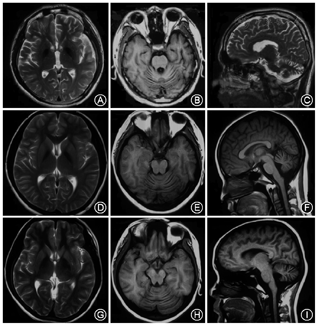

该家系中先证者(Ⅱ3)发病年龄17岁,临床主要表现为走路不稳,智力障碍、言语不清、肌张力障碍、癫痫、自主神经功能障碍,影像学表现为小脑萎缩、基底节区异常铁沉积。基因检测发现PLA2G6基因第3号外显子发生p.A80T,第7号外显子发生p.D331Y复合杂合突变,先证者两位姐姐(Ⅱ1,Ⅱ2)亦存在相同突变,先证者父亲携带p.A80T突变,母亲携带p.D331Y突变。先证者大姐(Ⅱ1)10岁左右发病,症状与先证者相似;先证者二姐(Ⅱ2)24岁开始出现步态异常;先证者两位姐姐(Ⅱ1,Ⅱ2)影像学均表现为小脑萎缩。

该家系种先证者(Ⅱ3),17岁时无明显诱因出现走路向后摔倒,2~3个月后逐渐出现不能自行走路(协调不好);至当地医院行头颅MRI检查,回示:基底节区异常铁沉积,小脑萎缩(图2)。18岁时逐渐出现全身肌张力增高,言语不清,生活不能自理,智力下降;上述症状进行性加重;至我院就诊,行体格检查示:面部表情呆,记忆力下降,思维迟钝,情感淡漠,智能下降,言语不清,颅神经检查正常,双上肢肌力5级,肌强直,腱反射亢进,Hoffmann征阳性,双下肢肌力为5级,肌张力增高,膝反射亢进,踝反射亢进,踝阵挛阳性,双侧Babinski征阳性,Pussep征阳性,Chaddock征阳性。四肢深浅感觉不配合,共济运动不配合。给予对症支持治疗,效果不佳。电话随访,患者19岁时出现频发癫痫,进食困难,伴大小便失禁,伴双上肢冰凉、汗多,进行性加重,20岁去世。

先证者大姐(Ⅱ1),10岁左右开始出现走路身体摇晃,15岁时至当地医院行头颅MRI检查,结果回示:小脑萎缩(图2);23岁时出现走路易跌倒,不协调,上述症状进行性加重;24岁开始出现智力下降、言语不清、吞咽困难、大小便失禁。2018年1月25日随访,患者25岁,查体与先证者相似。

先证者二姐(Ⅱ3),22岁开始走路姿势稍异常,自小视力差,余无特殊;2018年1月25日随访时24岁,查体视力差,共济稍差,余无特殊。其于14岁时(无症状)于当地行头颅MRI检查结果回示:小脑萎缩(图2)。

本研究报道了1个由PLA2G6基因突变所致不典型神经轴索营养不良家系的临床及影像学特征。典型的INAD患儿通常于6个月至3岁起病,临床以进行性运动障碍、智力低下,躯干性肌张力障碍、锥体束征阳性以及视力障碍为特征,部分患者晚期合并有癫痫发作[7];病情进展较快,患儿多于10岁前去世[8]。与INAD患者相比,不典型NAD有较大的表型变异,发病年龄较晚,多于4岁左右起病[9],有的也可晚至20岁[3],病情进展较慢,但其临床症状体征与INAD相似,可伴有不同形式的步态不稳、共济失调、社交障碍、言语障碍以及自闭症特征[4,7]。INADA与不典型NAD影像学均可表现为小脑萎缩伴或不伴有基节区异常铁沉积[10]。本研究纳入的家系特点主要为:发病年龄从17岁、10岁、22岁不等,临床表现早期以步态不稳,各种形式的共济失调为特征,后期伴有智能下降、言语不清、肌张力障碍、锥体束征阳性,三位患者影像学均表现为小脑萎缩,先证者影像学伴有基底节区异常铁沉积,另两位患者不伴有铁沉积。与文献报道的不典型神经轴索营养不良临床特征相一致。但患者(Ⅱ1、Ⅱ3)晚期伴有自主神经功能障碍,考虑为疾病晚期机体全面退行性变,累及自主神经所致。